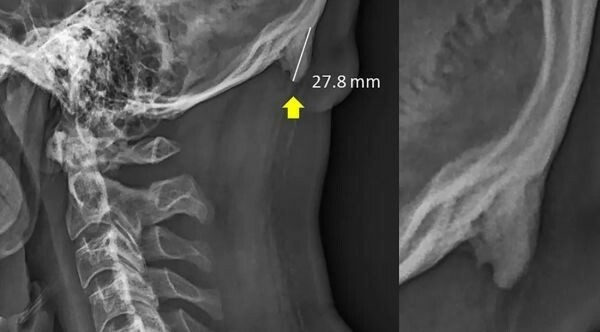

Шахар опубликовал своё исследование ещё в феврале 2018 года, однако оно разошлось в СМИ и соцсетях после материала «Би-би-си» в июне 2019 года. В первоначальной версии публикации говорилось, что смартфоны приводят к образованию отростков у подростков.

По версии Шахара, «рог» вырастает из-за необходимости наклонять голову вперёд, чтобы всматриваться в маленький экран. Он утверждал, что это приводит к переносу веса с позвоночника на мышцы затылка и образованию новой кости.